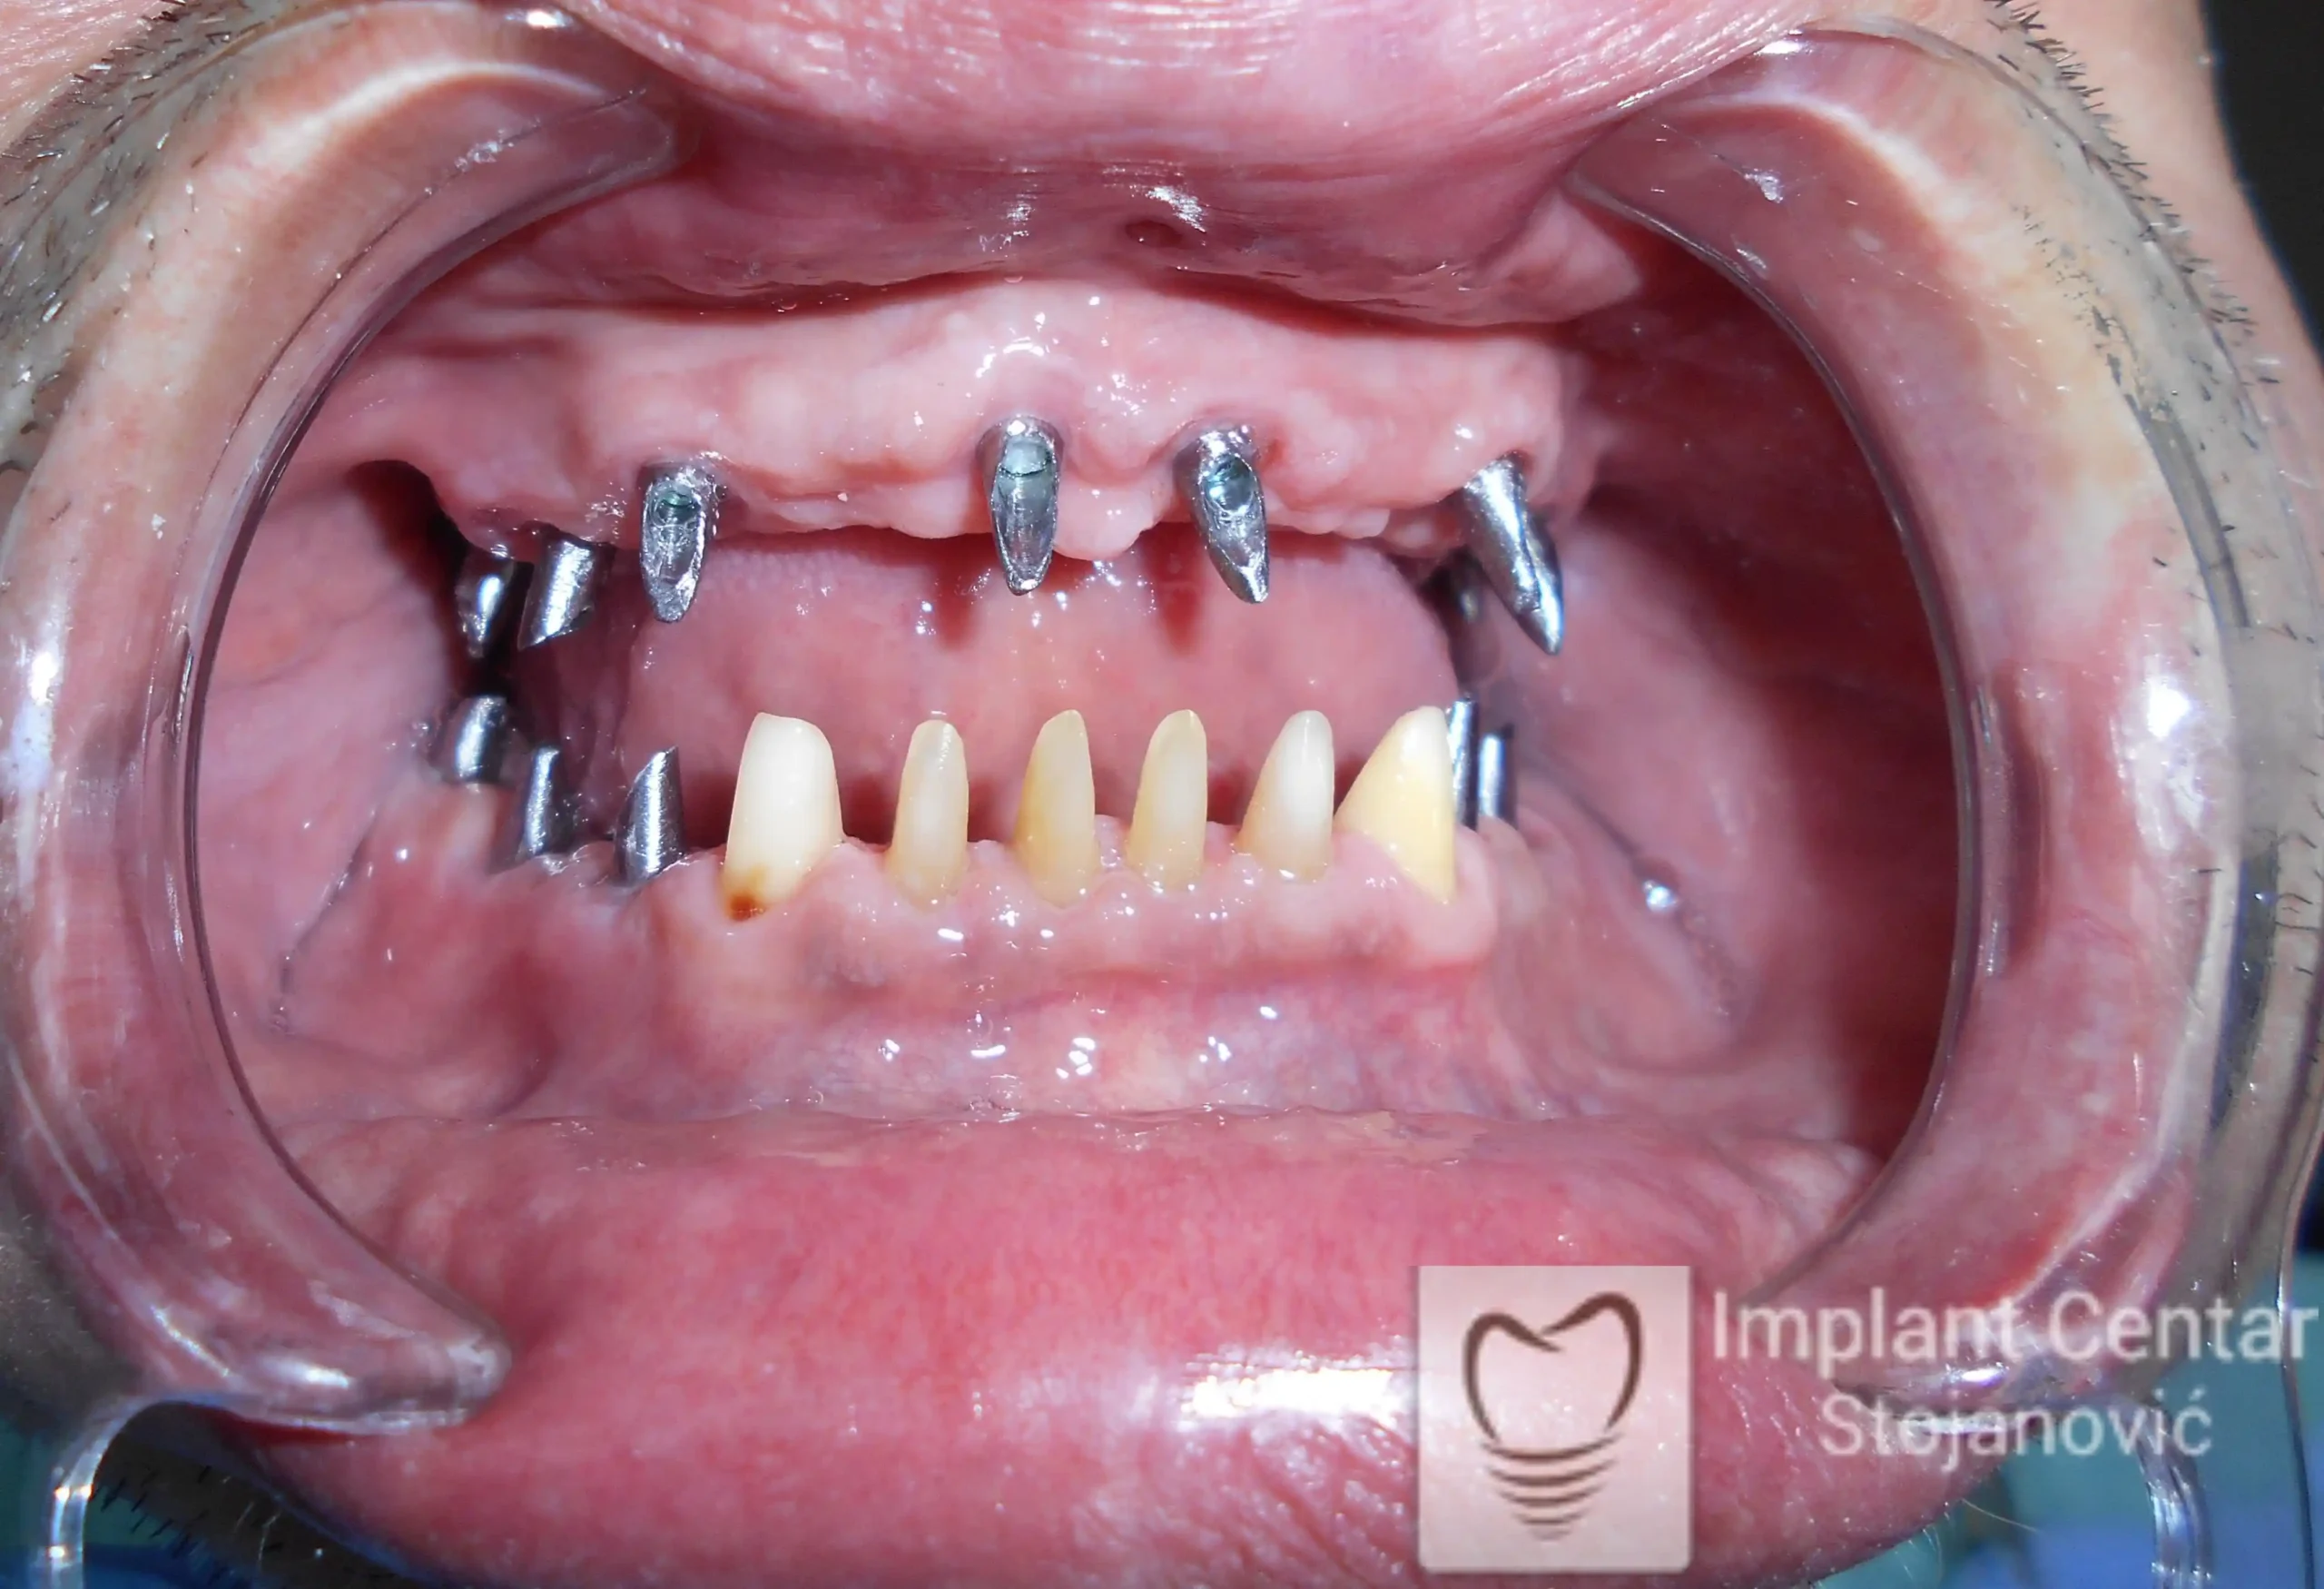

Pacijent sa rascepom usne, nepca i alveolarnog grebena uspešno je rehabilitovan fiksnim protetskim radom na implantatima. Pre dolaska u našu ordinaciju, pacijent je u gornjoj vilici nosio totalnu protezu preko preostalih zuba, dok je u donjoj vilici bio zbrinut parcijalnom mobilnom protezom. Tokom višegodišnje potrage za adekvatnim rešenjem, pacijent nije uspeo da pronađe zadovoljavajuću terapijsku opciju ni u zemlji ni u inostranstvu.

Nakon detaljnog kliničkog pregleda i analize radioloških snimaka, izrađen je sveobuhvatan plan terapije sa ciljem uklanjanja mobilnih proteza i postizanja maksimalne funkcionalne i estetske rehabilitacije. Zbog loše biološke vrednosti preostalih zuba, doneta je odluka o njihovom vađenju i ugradnji dentalnih implantata.

Poseban terapijski izazov predstavljalo je premošćavanje defekta nastalog usled rascepa, kao i ograničena količina raspoložive kosti u gornjoj vilici. Primenom većeg broja implantata i odgovarajućih procedura nadoknade kosti, postignuta je stabilna osnova za fiksni protetski rad.

Tokom perioda oseointegracije, pacijent je bio zbrinut fiksnim privremenim krunicama, čime je već pet dana nakon intervencije obezbeđena potpuna funkcionalna i estetska rehabilitacija. Nakon završetka perioda integracije implantata, izrađeni su definitivni cirkonijum-keramički mostovi na implantatima.